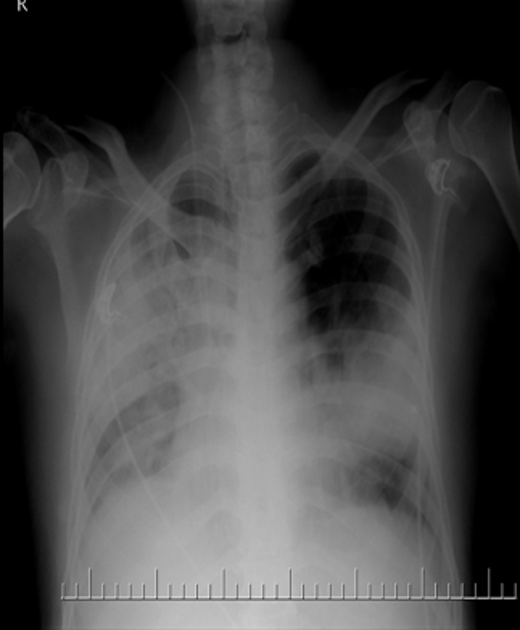

These are abnormal fluids or air accumulations in the chest or abdomen. They cause pain and breathlessness, needing urgent drainage.